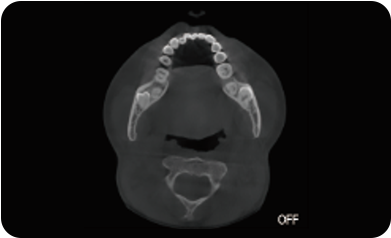

采用高性能CMOS探测器,最大FOV可达16x9cm星垂视野并支持无极可调,最小体素0.05mm。头颅采集模式,支持3s超快速扫描,最小像素99um,保证优质影像快速采集。

可根据临床需求任意调整成像区域大小实现局部超清三维显示

临床样片